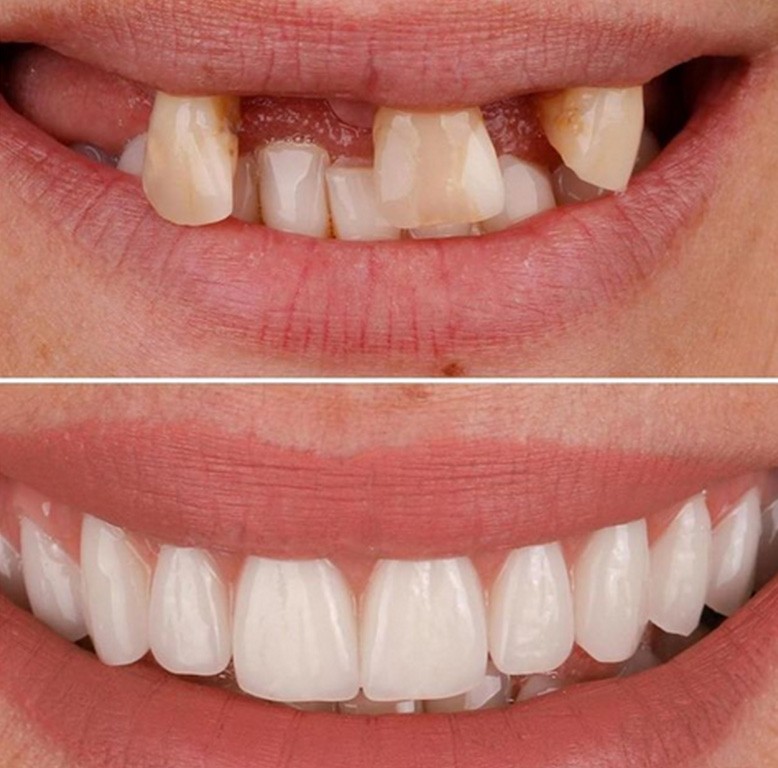

به دلایل مختلفی امکان دارد که فرد دندان اصلی رااز دست بدهد. امکان دارد یه آسیب فیزیکی باعث...

دندانپزشک متخصص ترمیم دندان ، در یک مطب یا کلینیک دندانپزشکی، مسئول حذف پوسیدگی ها، جبران...